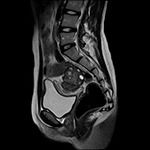

МРТ органов малого таза